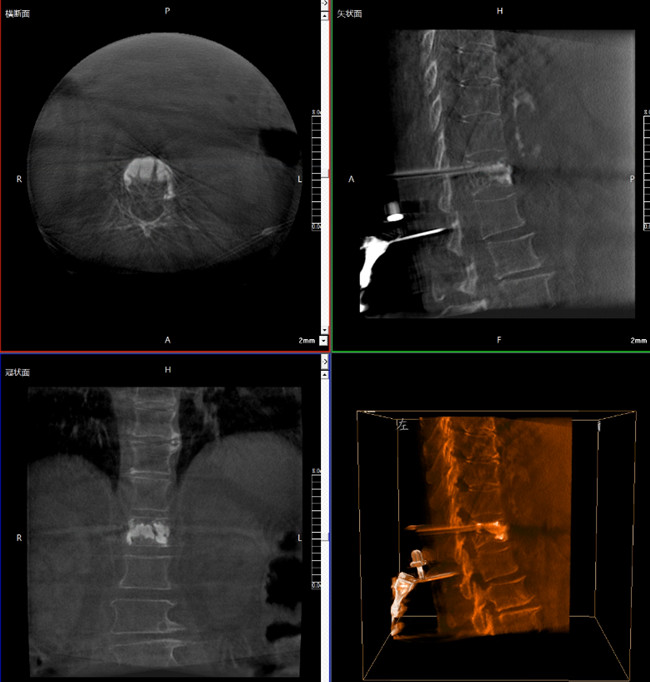

步驟一:C形臂三維重建+機器人手術規(guī)劃

使用普愛醫(yī)療三維C形臂對患者進行胸椎影像掃描及三維重建,圖像被同步傳輸?shù)狡諓坩t(yī)療骨科機器人導航系統(tǒng)。

借助骨科機器人的規(guī)劃軟件進行術前手術路徑模擬規(guī)劃,找到穿刺位置和角度,操作機械臂快速完成手術入點的準確定位。

*術前規(guī)劃